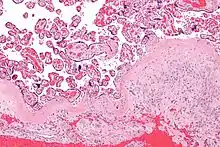

Капсульна децидуальна оболонка, розтягнута плідним міхуром, починає атрофуватися з кінця 2-го місяця. Надалі притискується плодом в процесі його росту до паріетальної й атрофується.

Паріетальна децидуальна оболонка з 6-го місяця стискується плодом у процесі його росту і зазнає зворотного розвитку, при цьому епітелій на її поверхні і в залозах зникає, з винятком найглибших відділів. Ампулоподібні кінці залоз стискуються й утворюють щілини.

Децидуальна оболонка відторгається разом з плацентою невдовзі після пологів. Залишки виходять з кров'ю на першому етапі лохій[3].